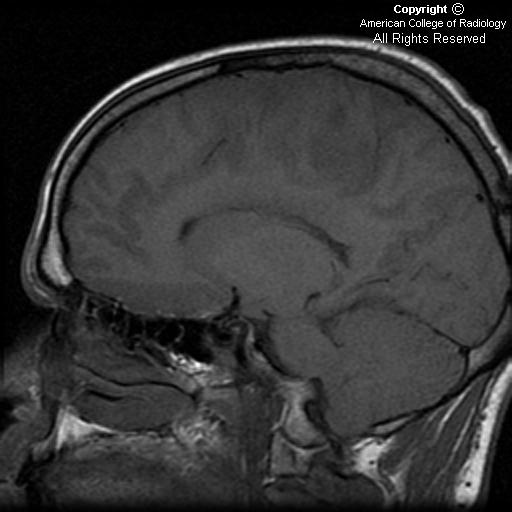

Alla risonanza magnetica la neoplasia appare come una lesione diffusa, poco circoscritta, infiltrante e senza enhancement, con segnale iperintenso nelle immagini pesate T2, e che si espande verso la materia bianca. È difficile da distinguere da un astrocitoma anaplastico altamente infiltrante o da un glioblastoma.